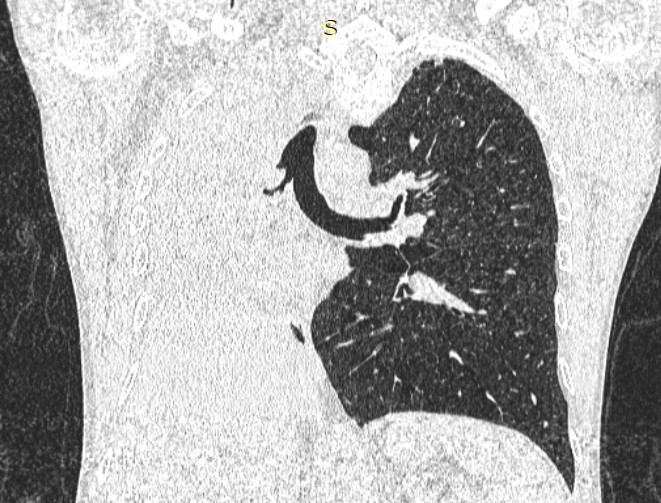

- გულმკერდის კტ კორონარულ ჭრილში 2 თვით ადრე.